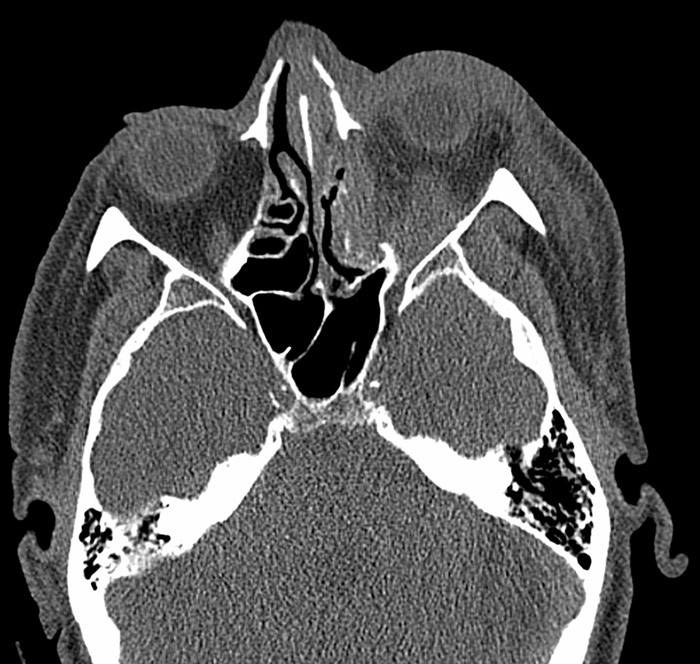

En mann i 60-årene ble innlagt etter en fallskade med traume mot ansiktsregionen. CT av ansikt viste nesefraktur, venstresidig fraktur av orbitagulvet og mediale orbitavegg med dislokasjon samt intraorbitalt hematom. Bulbus var intakt (bildet til venstre). Klinisk undersøkelse viste venstresidig periorbitalt hematom og uttalt proptose. Ved palpasjon var venstre øye spent uten elastisitet. Det forelå svært innskrenket øyebevegelighet av venstre øye i samtlige blikkretninger, nærmest oftalmoplegi. Det var verken direkte eller indirekte lysreaksjon og fullstendig tap av synet på venstre øye. Intraokulært trykk på venstre øye var målt til 70 mm Hg.

Bruddskader i orbita kan medføre blødninger som gir intraorbital trykkstigning med risiko for permanent synstap. Tilstanden er sjelden og benevnes som traumatisk retrobulbær blødning. Den affiserer 0,3 – 0,6  % av pasienter med zygomatikoorbitale frakturer (1). Traumatisk retrobulbær blødning kan føre til kompartmentsyndrom og krever rask intervensjon for å hindre irreversibel skade som kan oppstå etter 90 – 120 minutters mangel på tilstrekkelig blodforsyning i orbita. Tilstanden kan utvikles rett etter skaden eller flere timer senere.

Ved traumatisk retrobulbær blødning skaper blødning og ødem økt intraorbitalt trykk i septum orbitale. Når trykket øker, presses orbitainnholdet mot nervus opticus, og iskemiske skader oppstår grunnet kompresjon av intraorbitale kar. Det er uavklart om det er det direkte trykket mot nervus opticus, kompresjon av karforsyningen til nerven eller redusert blodforsyning i arteria centralis retina som gir synstap. Pasienter som er antikoagulert er særlig utsatt for synstap. Det kliniske bildet domineres av smerte, proptose, redusert visus, subkonjunktivalblødning, periorbital hevelse, oftalmoplegi og eventuelt manglende afferent pupillrefleks. Visusreduksjon som utvikler seg gradvis kan være tegn på en reversibel kompresjonsskade og ikke direkte mekanisk skade. Intraokulært trykk kan også være svært forhøyet.

Vår pasient oppfylte alle kriterier for traumatisk retrobulbær blødning. Fire timer etter innkomst ble det utført dekompresjon ved lateral kantotomi og kantolyse i lokalanestesi (åpning av laterale øyevinkel og spalting av det laterale kantale ligament) (bildet til høyre). Etter operasjonen gikk proptosen raskt tilbake og etter 15 minutter var det intraokulært trykk på 20 mm Hg. Pasienten fikk dessverre ikke bedre syn i dette tilfellet. Traumatisk optikusnevropati vurderes derfor som en mulig tilleggsdiagnose.